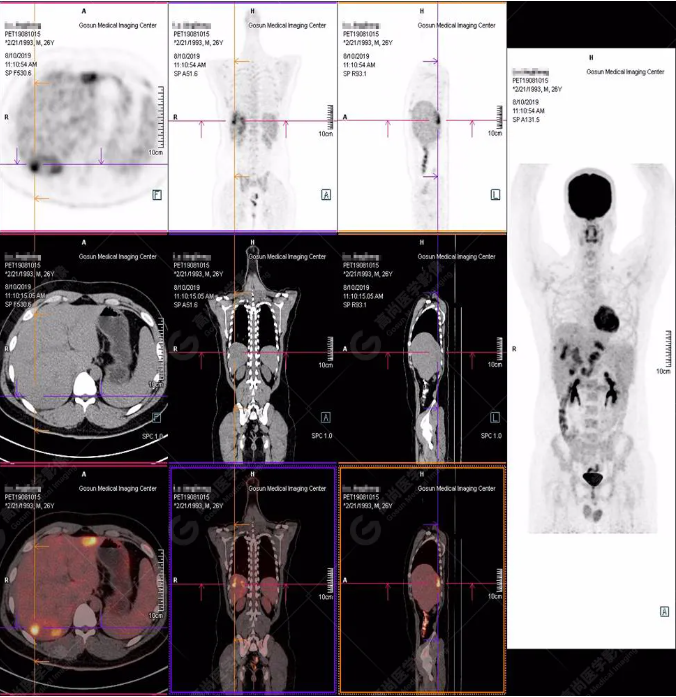

PET/CT全身圖

PET/CT診斷

嗜酸性粒細(xì)胞增多癥肝浸潤(rùn)